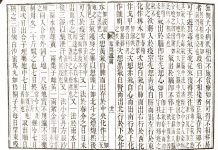

先日撮影した

写真を添えます。